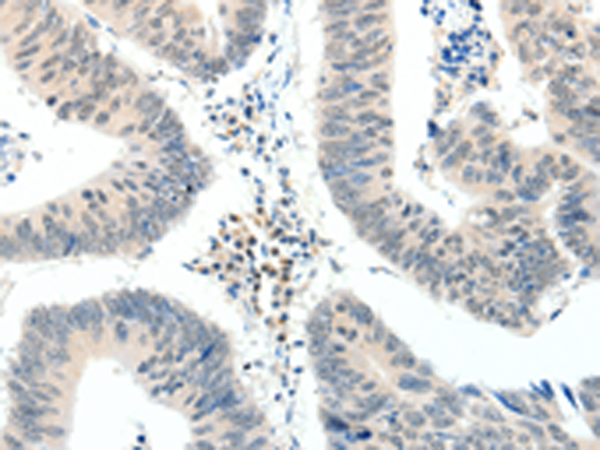

分类: 科研抗体货号: P04223别名: TOP2; TP2A应用: IHC反应种属: Human, Mouse, Rat